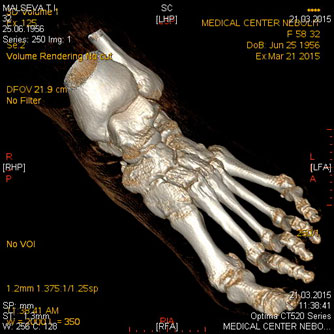

Компьютерная томография костей и суставов

Показания:

- подозрение на опухоль, метастатическое поражение

- воспалительные поражения (специфические, неспецифические)

- дегенеративно- дистрофические процессы

- врожденные аномалии развития